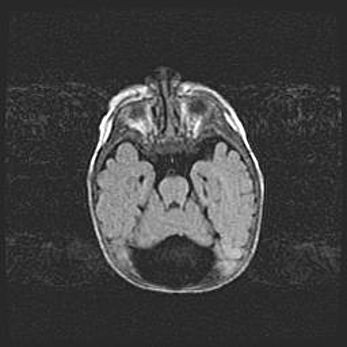

Сообщающаяся гидроцефалия. Кистозная энцефаломаляция головного мозга.

Возраст: 3 месяца 4 дня

Вес: 3100 г

Пол: женский

Окружность головы: 34 см

Срок гестации: 31 неделя

Кистозная энцефаломаляция головного мозга - одна из форм поражения головного мозга в детском возрасте. Характеризуется возникновением множественных и распространённых кист в коре, белом веществе и подкорковых образованиях головного мозга у плодов, новорождённых и детей раннего возраста. Развитие кистозной энцефаломаляции связано с внутриутробной асфиксией и гипотонией, родовой травмой, тромбозом синусов, пороками развития сосудов, инфекциями, сепсисом и другими причинами. Наиболее значимые инфекционные агенты: вирусы простого герпеса, цитомегалии, краснухи, токсоплазмы, энтеробактерии, золотистый стафилококк и другие.